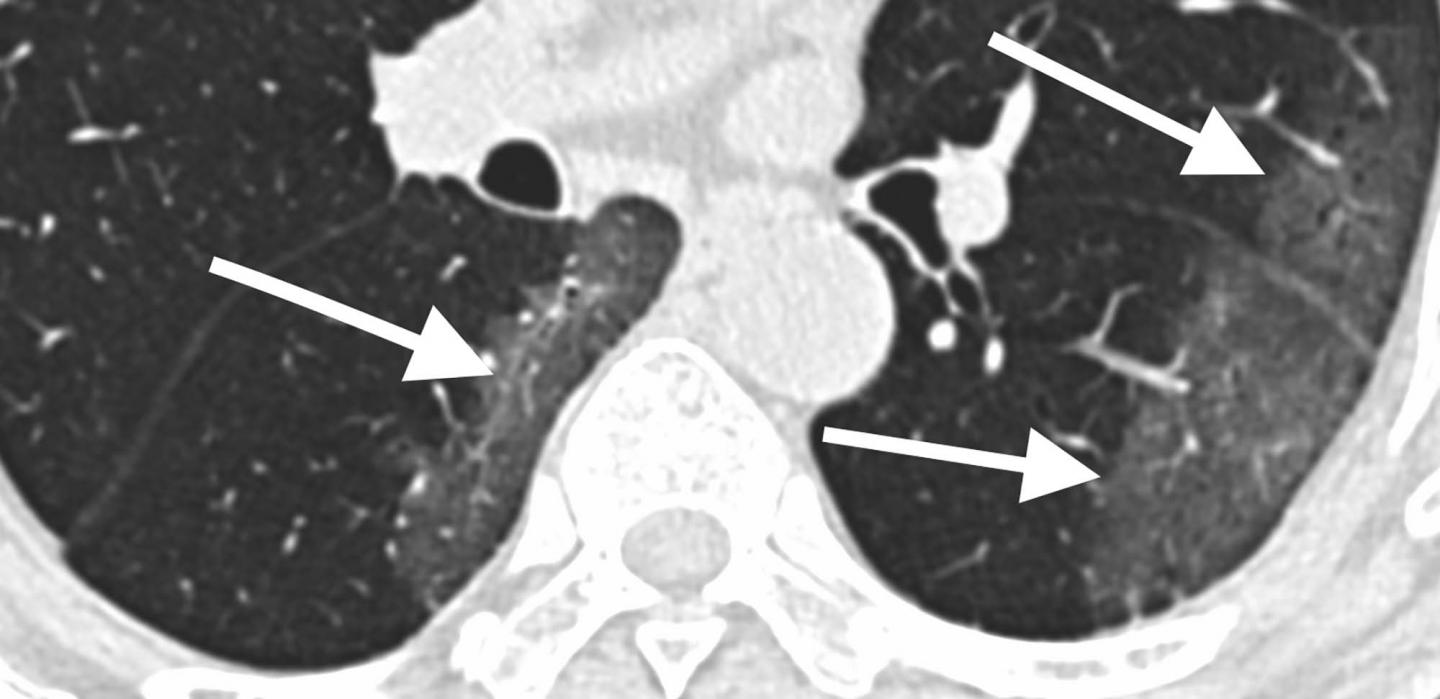

The analysis showed that 2019-nCoV typically manifests on CT with bilateral ground-glass and consolidative pulmonary opacities. Nodular opacities, crazy-paving pattern, and a peripheral distribution of disease may be additional features helpful in early diagnosis. The researchers also noted that lung cavitation, discrete pulmonary nodules, pleural effusions and lymphadenopathy are characteristically absent in cases of 2019-nCoV.

For each of the 21 patients, the initial CT scan was evaluated for the following characteristics: (1) presence of ground-glass opacities, (2) presence of consolidation, (3) number of lobes affected by ground-glass or consolidative opacities, (4) degree of lobe involvement in addition to overall lung "total severity score," (5) presence of nodules, (6) presence of a pleural effusion, (7) presence of thoracic lymphadenopathy (lymph nodes of abnormal size or morphology), and (8) presence of underlying lung disease such as emphysema or fibrosis. Any other thoracic abnormalities were also noted.